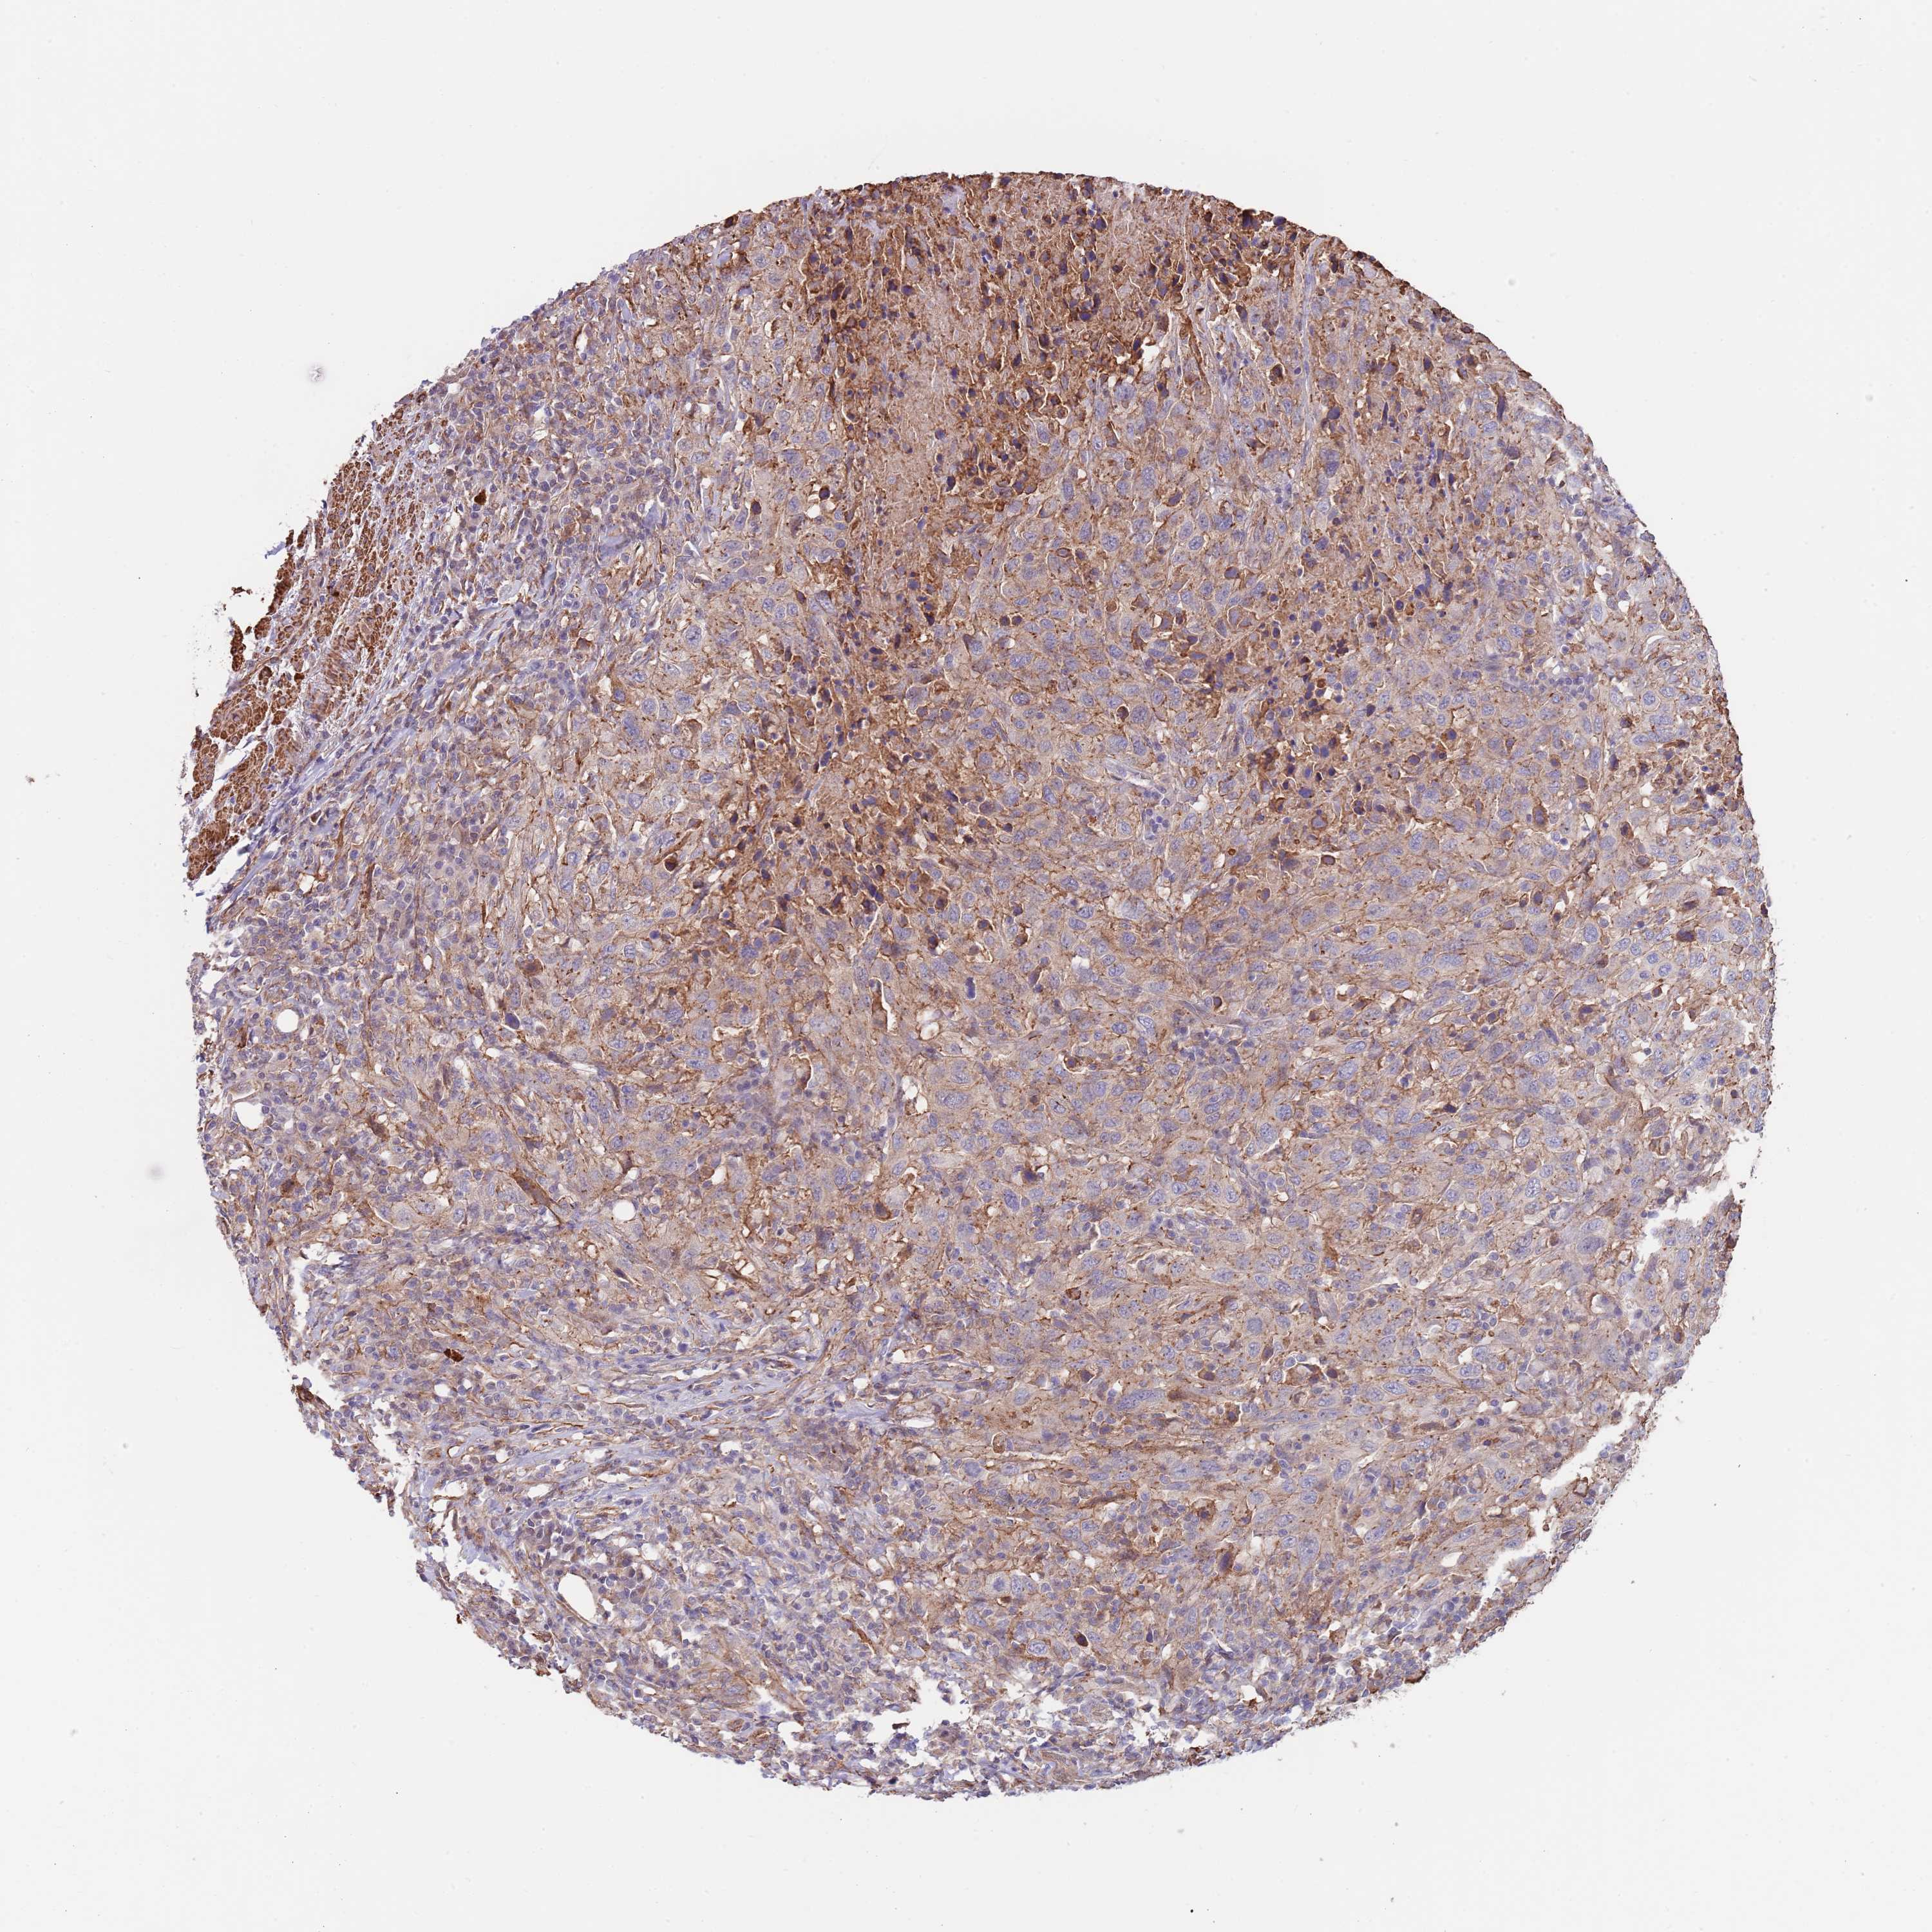

UROTHELIAL CANCER - Protein expressioni

A mouse-over function shows sample information and annotation data. Click on an image to view it in a full screen mode. Samples can be filtered based on level of antibody staining by selecting one or several of the following categories: high, medium, low and not detected. The assay and annotation is described here.

Note that samples used for immunohistochemistry by the Human Protein Atlas do not correspond to samples in the TCGA dataset.

Antibody stainingi

Antibody staining in the annotated cell types in the current human tissue is reported as not detected, low, medium, or high, based on conventional immunohistochemistry profiling in selected tissues. This score is based on the combination of the staining intensity and fraction of stained cells.

Each image is clickable and will lead to virtual microscopy that enables deeper exploration of all samples and also displays staining intensity scores, fraction scores and subcellular localization as well as patient and tissue information for each sample.

Antibody HPA048461

Staining

High

Medium

Low

Not detected

Intensity

Strong

Moderate

Weak

Negative

Quantity

>75%

75%-25%

<25%

None

Location

Nuclear

Cytoplasmic/membranous

Cytoplasmic/membranous,nuclear

Urothelial carcinoma, Low grade

Urothelial carcinoma, High grade

Urothelial carcinoma, NOS